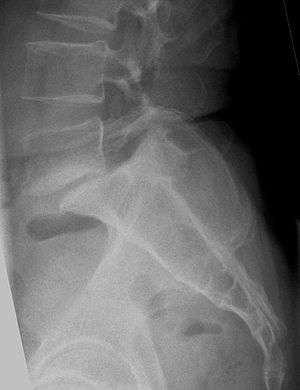

| X-ray of the lateral lumbar spine with a grade III spondylolisthesis at the L5-S1 level. | |

Spondylolisthesis /ˌspɒndɪloʊlɪsˈθisɪs/ SPON-dill-oh-lis-THEE-sis is the forward displacement of a vertebral bone in relation to the natural curve of the spine, most commonly occurring after a fracture, and most often the fifth lumbar vertebra.[1] Backward displacement is referred to as retrolisthesis. When occurring in conjunction with scoliosis, the shortened term "olisthesis," may sometimes be used instead. [2]